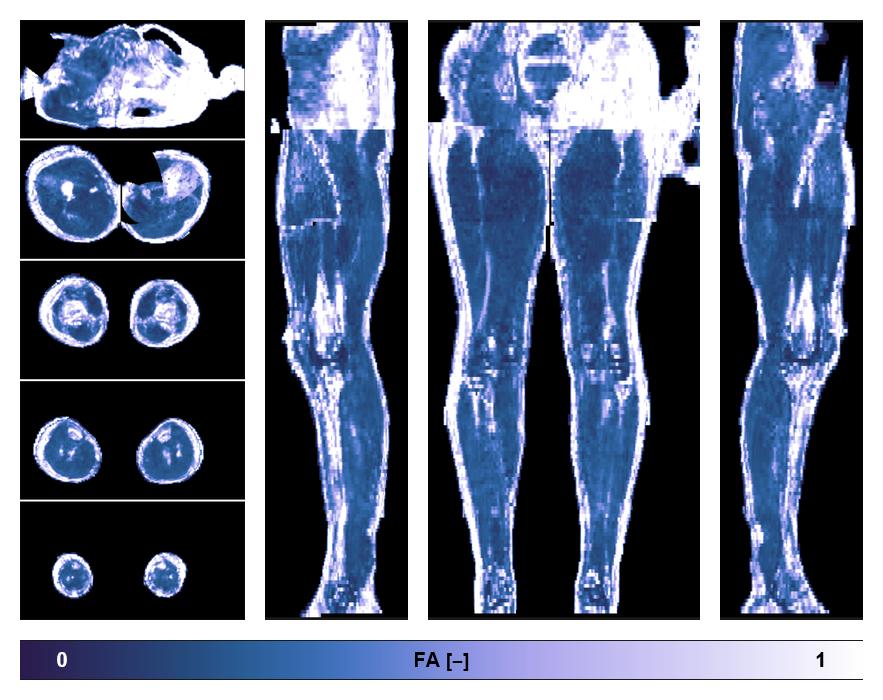

• Fractional anisotropy

IVIM corrected whole leg muscle fractional anisotropy obtained from diffusion tensor imaging.